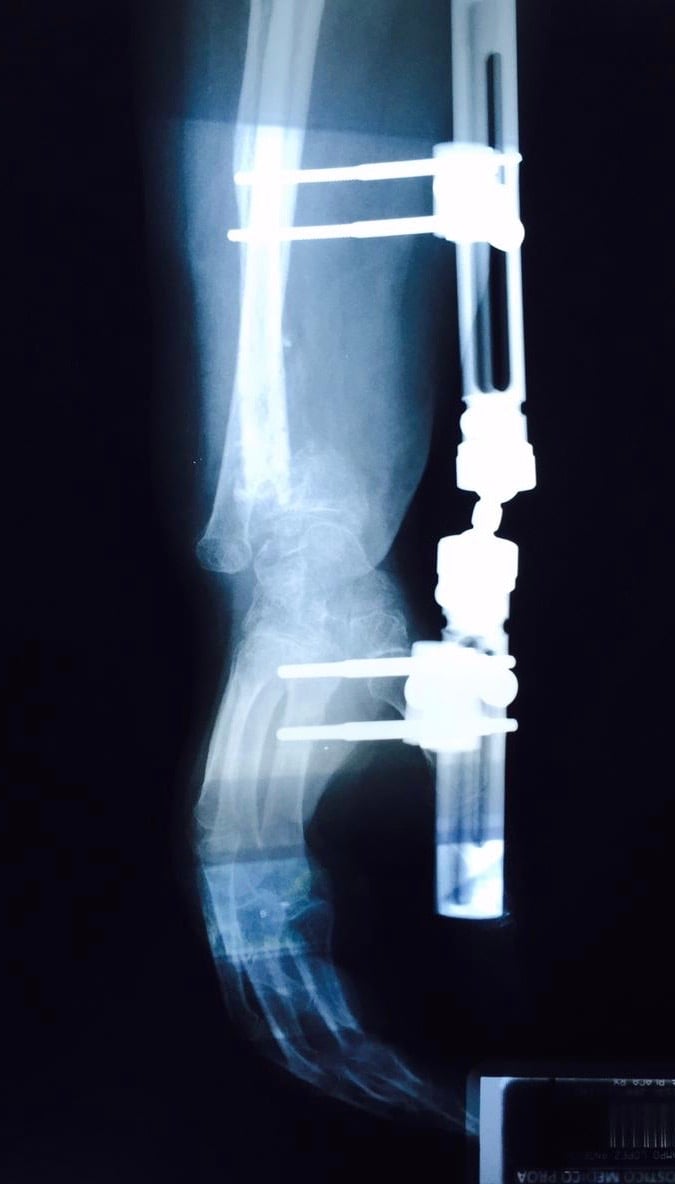

• Secuelas de: fracturas, fisuras, luxaciones, esguinces, tendinitis, tendinosis,  y desgarres musculares.

• Post operados de: Columna, Hombro, Codo, Muñeca, Mano y Dedos, Cadera, Rodilla, Tobillo y Pie

• Amputaciones (manejo de muñón, rehabilitación pre-protésica y protésica funcional)